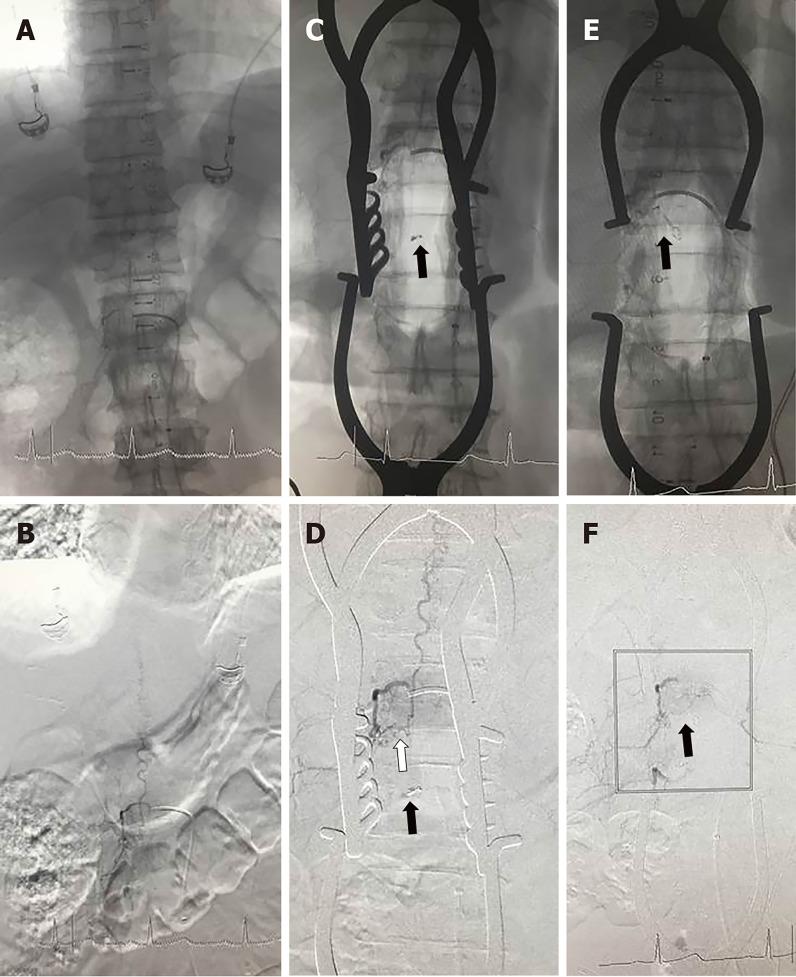

Eleven patients with SDAVFs were treated with the use of a hybrid-OR at the Department of Neurosurgery of our hospital between January 2015 and December 2018. The dual-marker localization technique was used in the hybrid-OR to locate the SDAVFs and skin incision, and the interoperative digital subtraction angiography (DSA) technique was used before and after microsurgical ligation of the fistulae in the hybrid-OR to verify the accuracy of obliteration. The patients were followed for an average of 2 years after the operation, and the preoperative American Spinal Cord Injury Association (ASIA) score and postoperative ASIA score at 6 mo after the operation were compared.

The location and skin incision of the SDAVFs were accurately obtained by using the dual-marker localization technique in the hybrid-OR in all patients, and there were no cases that required expansion of the range of the bone window in order to expose the lesions. Intraoperative error obliteration occurred and was identified in two patients by using the intraoperative DSA technique; therefore, the findings provided by the intraoperative DSA system significantly changed the surgical procedure in these two patients. With the assistance of the hybrid-OR, the feeding artery was correctly ligated in all cases, and the intraoperative error obliteration rate decreased from 18.2% (2/11) to 0%. All 11 patients were followed for an average of 2 years. The ASIA score at 6 mo after the operation was significantly improved compared with the preoperative ASIA score, and there were no patients with late recurrence during the follow-up.

Compared with intra-arterial embolization for the treatment of SDAVFs, hybrid-ORs can solve the problem of a higher incidence of initial failure and late recurrence. Compared with direct occlusion of SDAVFs in microsurgery, hybrid-ORs can take advantage of the intraoperative DSA system for locating the shunt and verifying the obliteration of fistulae in order to reduce the error obliteration rate. At this point, our experience suggests that the safety and ease of use make hybrid-ORs combined with microsurgery and intraoperative DSA systems an attractive modality for dealing with SDAVFs.